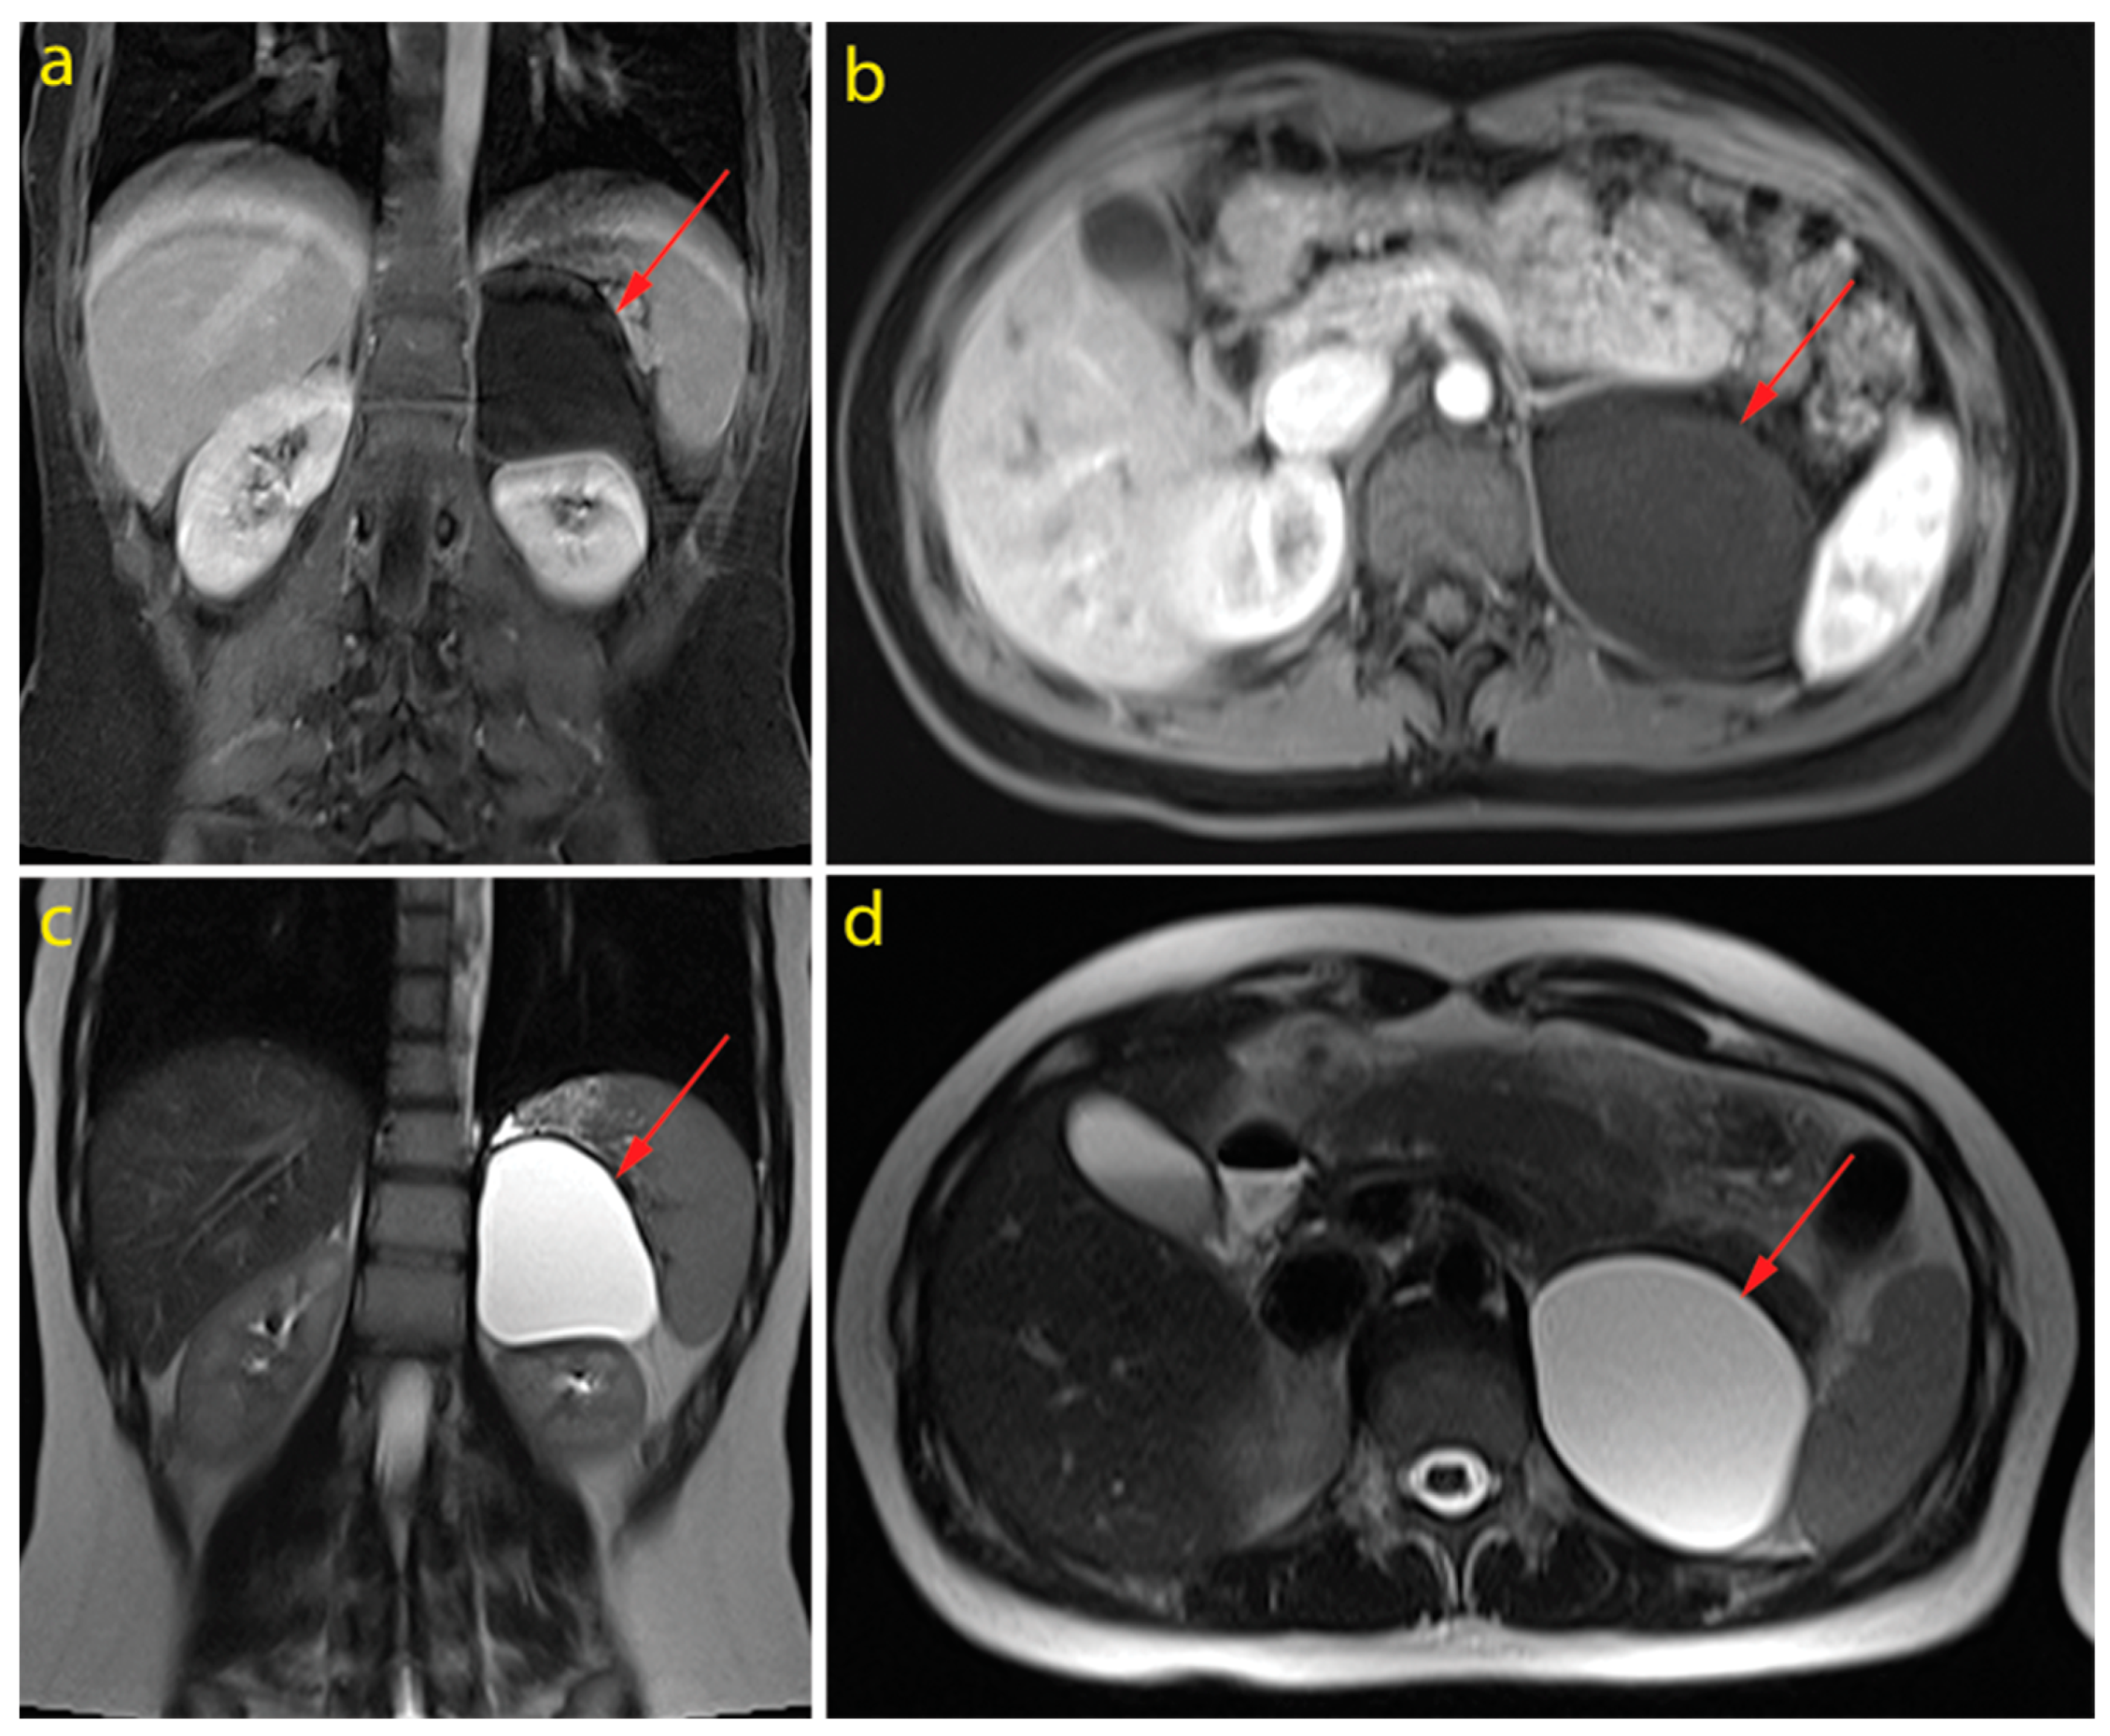

3. Case Description